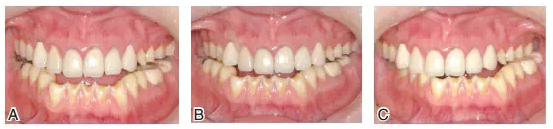

圖6患者J初診時(shí)的最大牙尖交錯(cuò)位咬合情況。上頜后牙及下頜前牙區(qū)重度磨耗,后牙區(qū)牙合曲線呈上凸的倒曲線